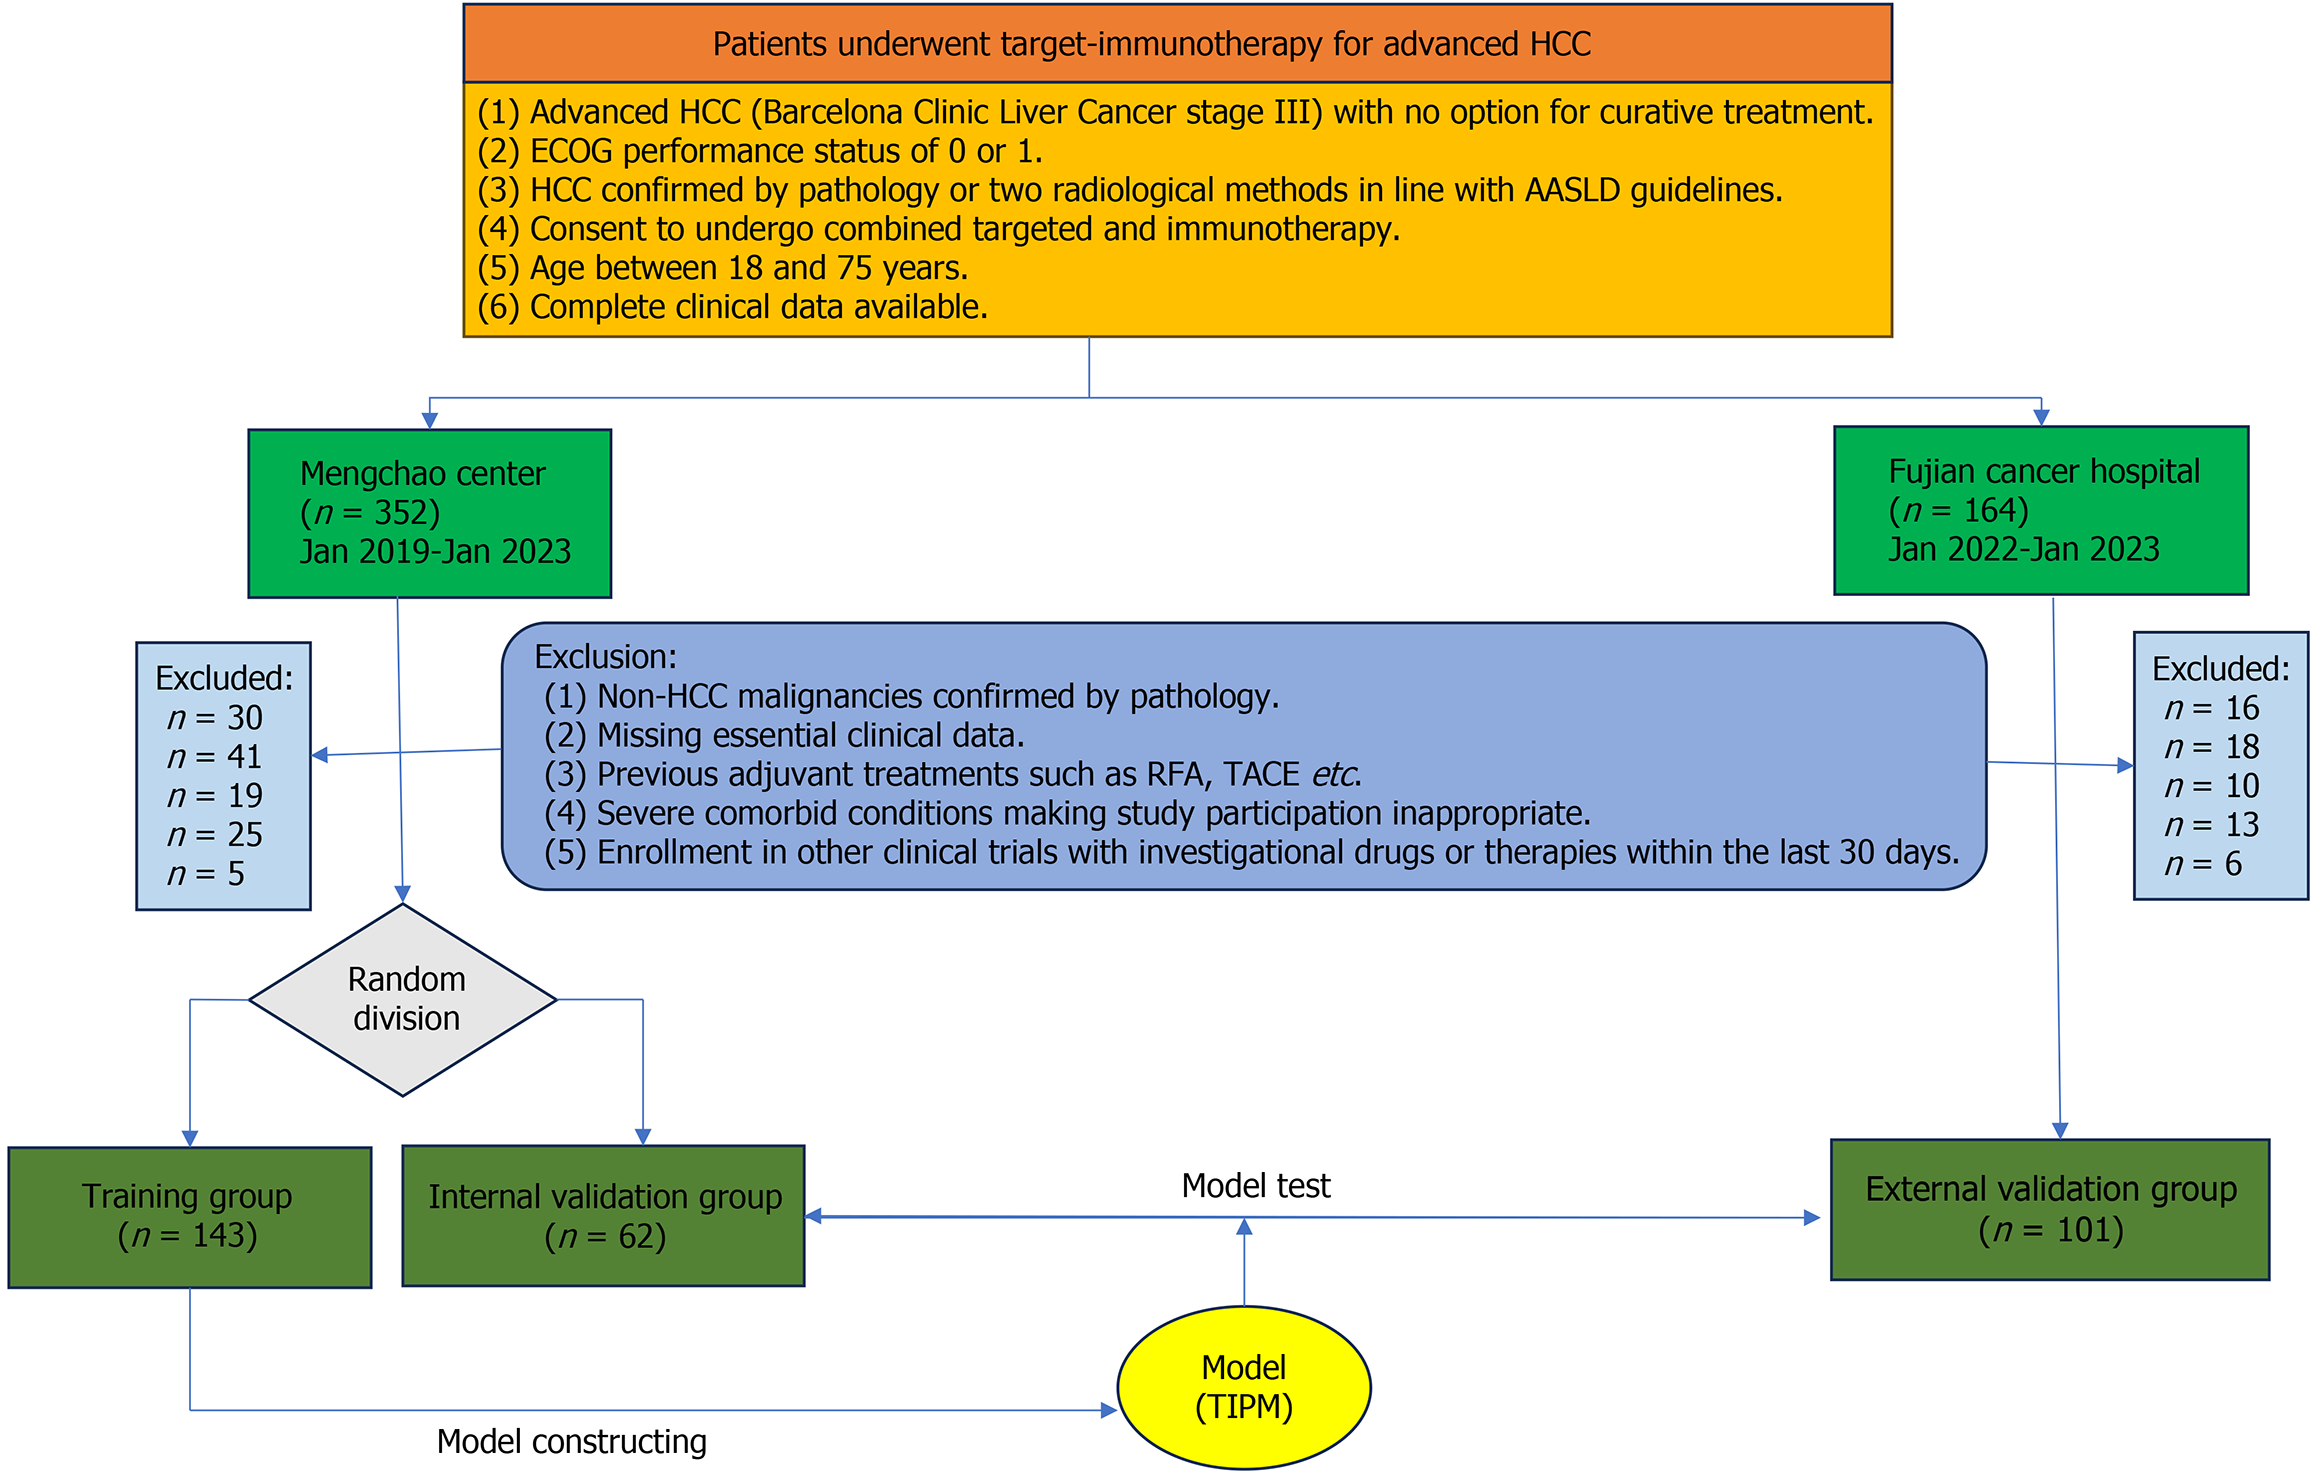

Figure 1 Patient selection diagram.

HCC: Hepatocellular carcinoma; ECGO: Eastern Cooperative Oncology Group; AASLD: American Association for the Study of Liver Diseases; RFA: Radiofrequency ablation; TACE: Transarterial chemoembolization; TIPM: Target Immunotherapy Predictive Model.